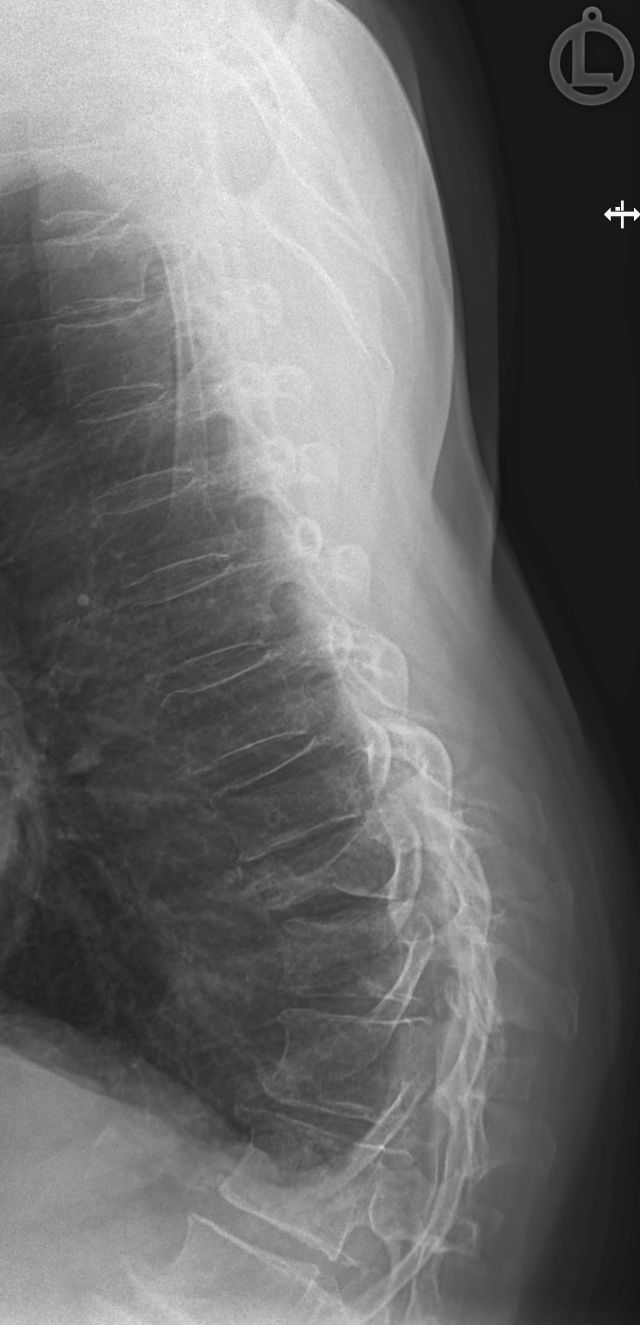

Röntgen der Lunge

Die Röntgenaufnahme der Lunge wird typischer Weise im Stehen am Wandstativ in zwei Ebenen in der Regel unter tiefer Einatmung durchgeführt. So können Veränderungen in der Lunge festgestellt und lokalisiert werden wie z.B. Tumoren, Lungenentzündung, Belüftungsprobleme von Lungenabschnitten und etliche andere Erkrankungen.